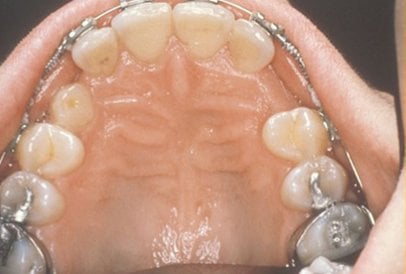

In cases where the eyeteeth will not erupt spontaneously, the orthodontist and oral surgeon will work together to get these teeth to erupt. Each case must be evaluated on an individual basis, but treatment will usually involve a combined effort between the orthodontist and the oral surgeon. The oral surgeon will expose and bracket the impacted eyetooth.

The goal is to erupt the impacted tooth and not to extract it. Once the tooth has moved into its final position, the gum around it will be evaluated. In some circumstances, there may be some minor “gum surgery” required.

Exposure and Bracketing of an Impacted Cuspid